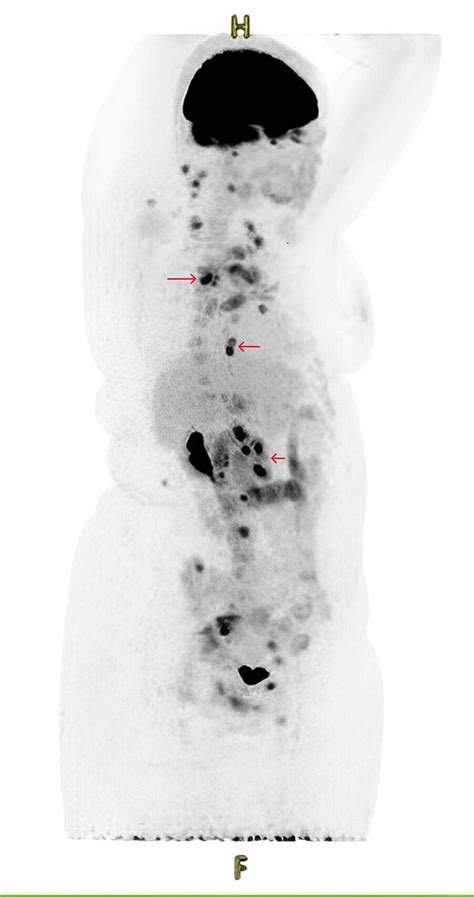

Furthermore, the Ann Arbor staging system is not static. It has evolved over time to incorporate new knowledge and technologies. For example, advancements in imaging techniques, such as PET scans, have allowed doctors to detect smaller and more subtle signs of lymphoma spread. These improvements have led to refinements in the staging criteria, making the system even more accurate and reliable. The system’s adaptability ensures it remains a relevant and valuable tool in the ever-changing landscape of cancer care. So, when you hear about the Ann Arbor staging system, remember that it’s a cornerstone of how we understand and fight Hodgkin lymphoma, guiding doctors in providing the best possible care to patients.

Accurate staging in Hodgkin lymphoma, guys, is super important because it directly influences treatment decisions, prognosis predictions, and overall patient management. When doctors correctly determine the stage of the disease using the Ann Arbor staging system, they can create treatment plans that are specifically tailored to the extent and characteristics of the lymphoma. This precision helps ensure that patients receive the most appropriate and effective care, maximizing their chances of achieving long-term remission and minimizing potential side effects. The staging process involves a thorough evaluation of the patient’s medical history, a physical examination, imaging studies (such as CT scans, PET scans, and MRI), and sometimes a bone marrow biopsy. These tests help doctors identify the location and extent of the lymphoma, as well as whether it has spread to other organs or tissues.